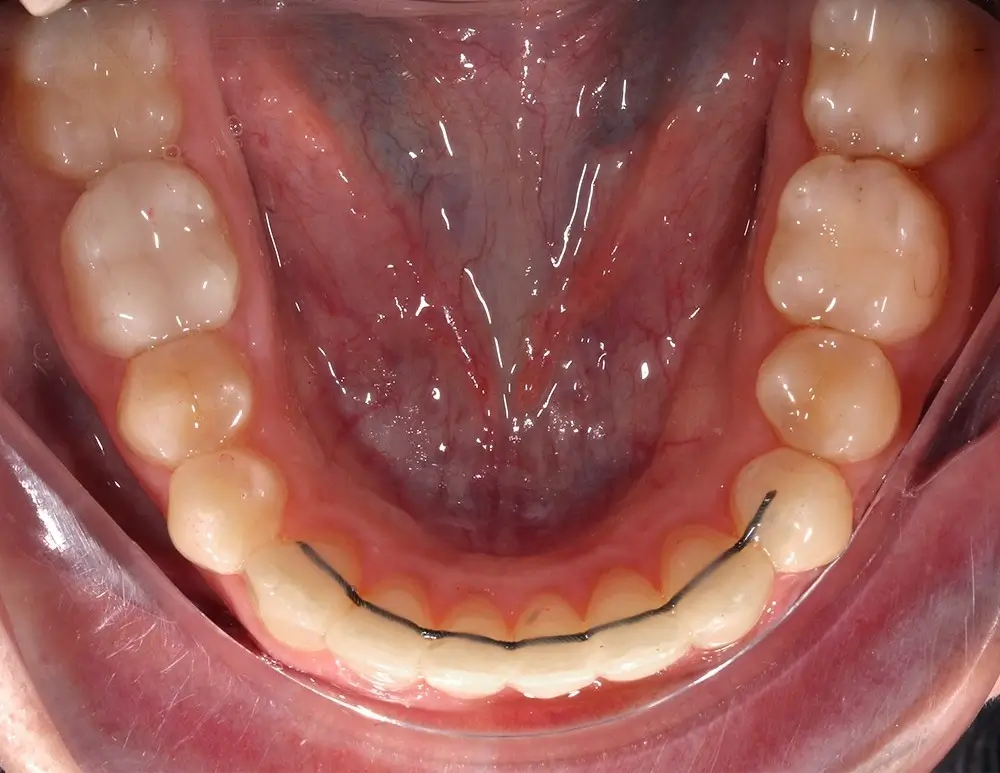

Кейс 13

Булгач (Мочалова) Галина Игоревна

Количество кап ВЧ 19

Количество кап НЧ 24

ДО

ПОСЛЕ